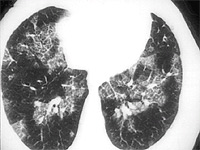

A 50 yo male was receiving home IV antibiotics for osteomyelitis of his hip. He was 7 weeks into his course of therapy when he began to develop low grade fevers. Over the next 2 weeks extensive work-up was done without revealing a source for the fever. The orthopedics service felt his osteomyelitis was responding to the therapy and that this was unlikely a source for his elevated temperature. About this time he began to experience dyspnea, which progressively worsened so he was admitted to the hospital for evaluation. Physical exam revealed T 100.8, R 16, P 82, BP 130/74; Right subclavian tunneled catheter; Lungs with scant bibasilar rales; CV with regular rhythm and no murmur; Extremities without cyanosis, clubbing, or edema. PFTs: FVC 3.98 L (83% predicted); FEV1 3.08 L (80% predicted); TLC 5.74 L (85% predicted); and DLCO 14.96 ml/min/mmHg (42% predicted).

CXR showing multiple nodules.

CT showing multiple small nodules

Diagnosis: Pulmonary Talcosis